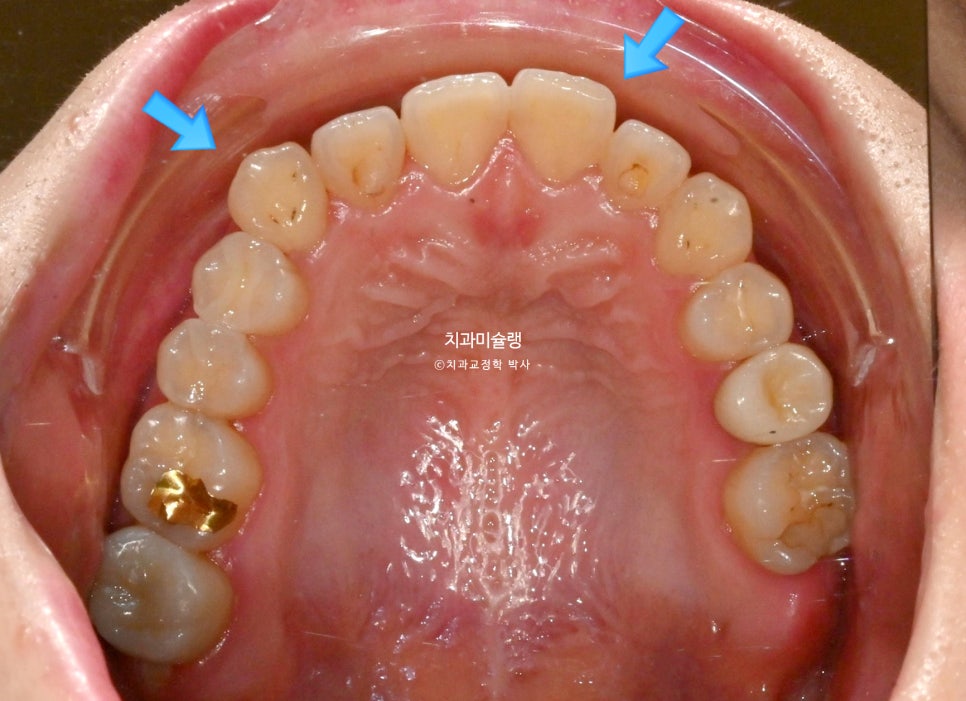

우측 송곳니가 내려와있고 앞니 치축이 위아래 둘다 전반적으로 기울어져 있습니다.

내려와있는 한쪽 송곳니, 기울어진 치축 때문에 비대칭의 느낌이 있습니다.

내려와있던 송곳니는 잘 올라갔으며 중심선은 처음보다 맞아졌습니다.

배열상 들쑥날쑥한 부분들도 가지런 해졌습니다.

중심선이 맞아졌으며 송곳니를 포함한 위 6개 앞니 높이가 균일해졌습니다.